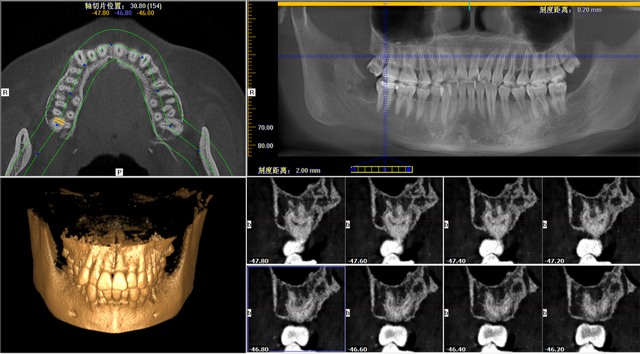

жӢ”зүҷд№ӢеүҚ���пјҢеӮ…еҗ•йҖҡиҝҮеҸЈи…”CT���пјҢи§Ғе‘ҠжҳҺеҘіеЈ«еҸіиҫ№дёҠйқўжҷәйҪҝзғӮзҡ„еҫҲж·ұ���пјҢйңҖе°Ҫеҝ«ж”ҫејғ��гҖӮдёҚдҪҶдә‘дә‘���пјҢеҸЈи…”CTиҝҳжҸҗйҶ’жҳҺеҘіеЈ«иҜҘжҷәйҪҝжңүеӣӣдёӘеҸҲејҜеҸҲз»Ҷзҡ„зүҷж №���пјҢзүҷж №зҰ»дёҠйўҢзӘҰеҫҲжҳҜиҝ‘���пјҢжё…йҷӨеҸҠжё…йҷӨжҺүиҗҪдёҠйўҢзӘҰзҡ„еҚұе®іиҫғеӨ§���пјҢе®Ңж•ҙжӢ”еҮәжқҘйҡҫеәҰеҫҲеӨ§��гҖӮ

жҳҺеҘіеЈ«еҸЈи…”CTеӣҫ